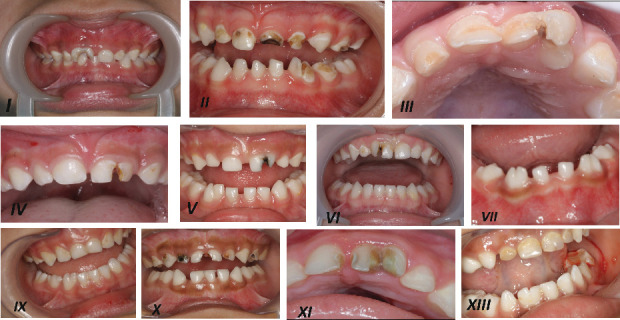

Fusion is a developmental dental anomaly that may affect both dentitions. The condition occurs during the developmental stage when two different tooth buds fuse. Depending on the degree of fusion, teeth may be diagnosed with fusion, gemination, or macrodontia. This defect is typically described as primary double teeth. The main clinical problems associated with primary double teeth include dental caries, crowding, occlusal discrepancies, and poor aesthetics. This report presents the clinical experience of managing 13 primary fused anterior teeth. The aim was to preserve and restore the decayed teeth while maintaining function and aesthetics. Treatment varied from the application of preventive measures to the separation of fused teeth. Clinical and radiographic diagnoses were used to determine the appropriate treatment plan. Decay removal was followed by restoration using either composite or zirconia crowns. Some teeth required pulp treatment before final restoration; therefore, pulpectomy was performed, and the canals were sealed with a calcium hydroxide and iodoform mix. Evaluation criteria included clinical success, gingival health, function, and aesthetic preservation. Follow-up periods ranged from 1 to 4 years. The follow-up of the presented cases demonstrated that the selected preventive, restorative, and surgical approaches successfully retained the affected teeth in a stable and healthy condition.